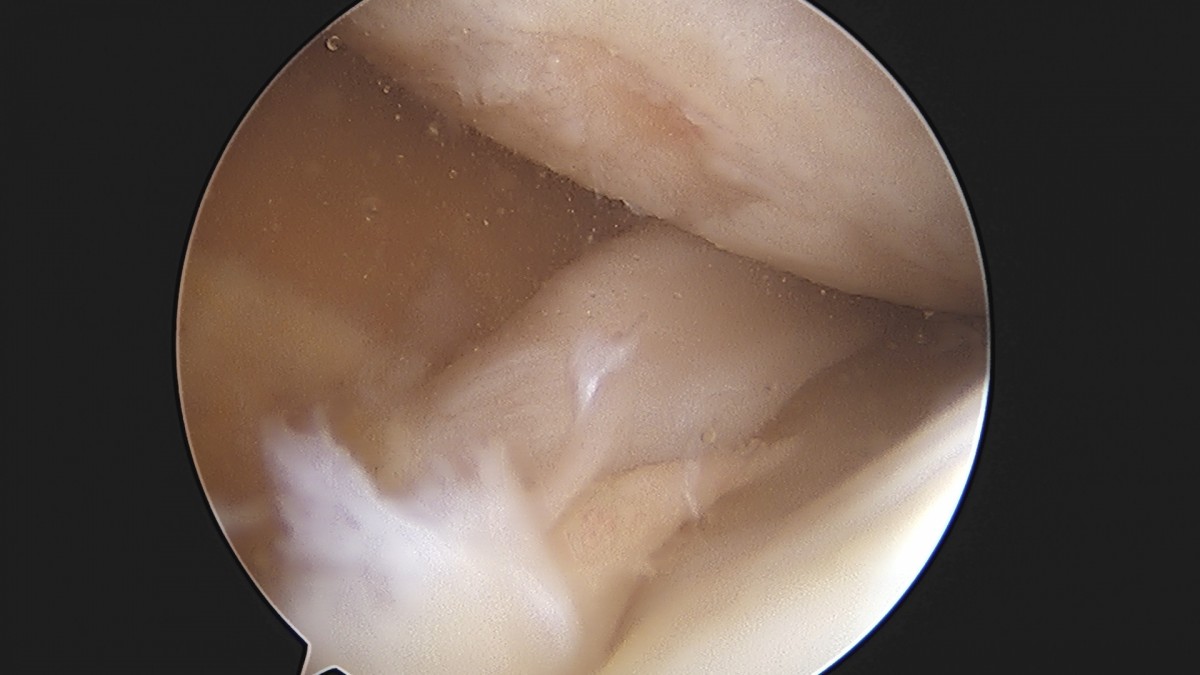

이재상원장님 무릎 반월상 연골판 절제술 김민O 환자

작성자 최고관리자 댓글 0건 조회 365회 작성일 25-09-16 16:10